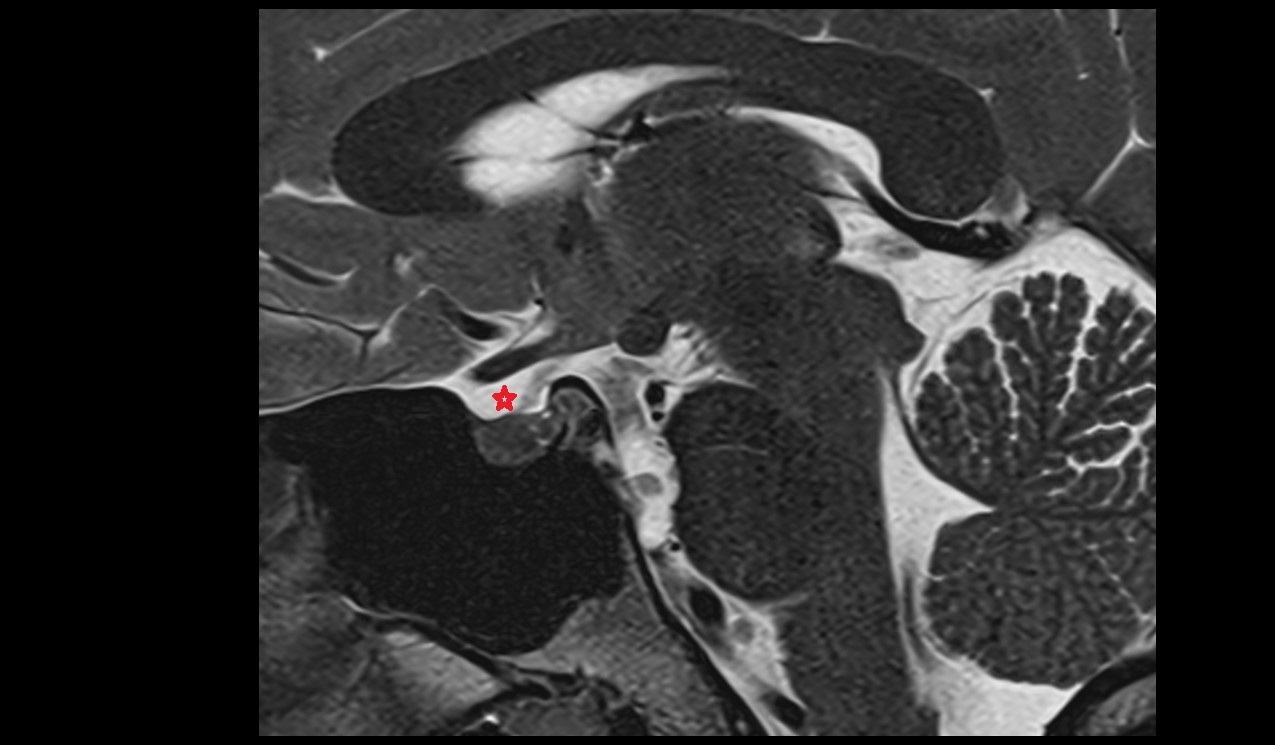

- Median aperture of fourth ventricle (foramen of Magendie)

- Lateral aperture of fourth ventricle (foramen of Luschka)